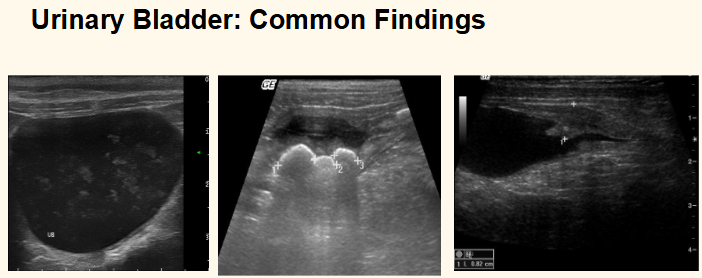

what are these 3 common findings in the urincary bladder